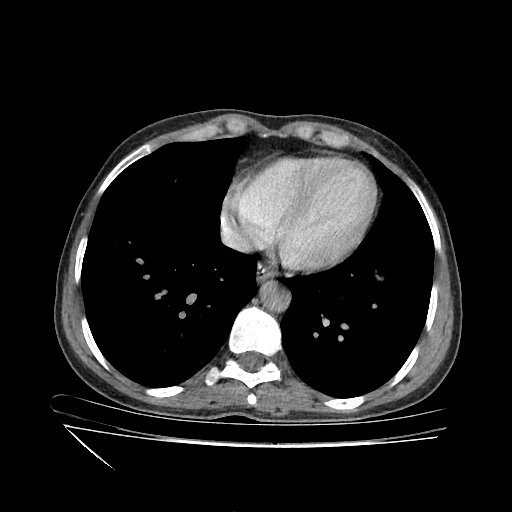

Original VENOUS CT scan

Full window (WL 1023.5, WW 4095 β†’ Low βˆ’1024, High +3071)

Actual HU range: [-160.0, 240.0]

Mediastinum window (WL 40, WW 400 β†’ Low βˆ’160, High +240)